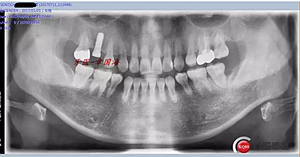

附另外一種植前后圖: